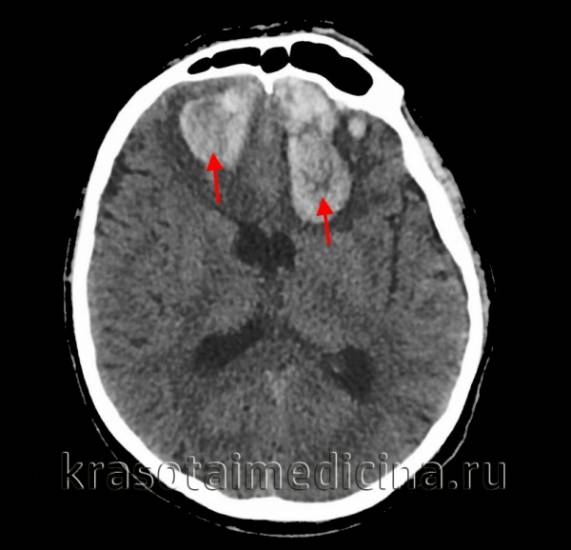

• КТ головного мозга. На томограммах внутримозговая гематома выглядит как очаг гомогенной плотности округлой или овальной формы. Если гематома возникла из-за ушиба головного мозга, она обычно имеет неровные контуры. Со временем плотность гематомы уменьшается до изоплотного состояния, соответствующего плотности мозговой ткани. Для малых гематом этот процесс занимает 2-3 недели, для средних — до 5 недель.

• МРТ головного мозга. При снижении плотности гематома лучше визуализируется с помощью МРТ. Однако на ранних стадиях МРТ может привести к ошибочному диагнозу, принимая гематому за опухоль с кровоизлиянием. Поэтому многие неврологи и нейрохирурги предпочитают использовать оба метода (КТ и МРТ) для диагностики.